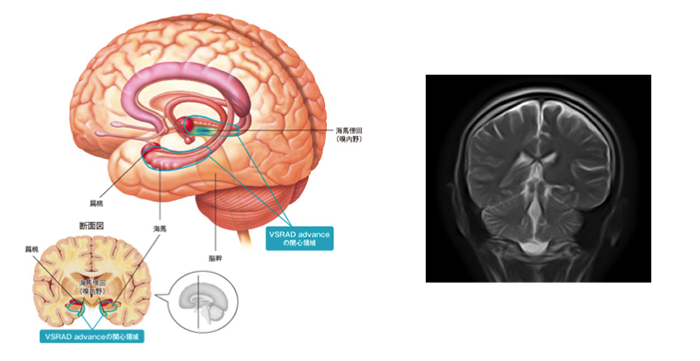

脳ドック基本コースに加え記憶領域を司るといわれる海馬の検査を行います。早期アルツハイマー型認知症が確認できます。

早期の認知症 では最も早く海馬傍回(記憶に関わる部位) が萎縮することがわかっています。MRI 画像を利用し、この海馬傍回の体積の萎縮度を正常脳と比較します。また認知症のなかでも手術で良くなる可能性がある正常圧水頭症の有無も併せて確認できます。